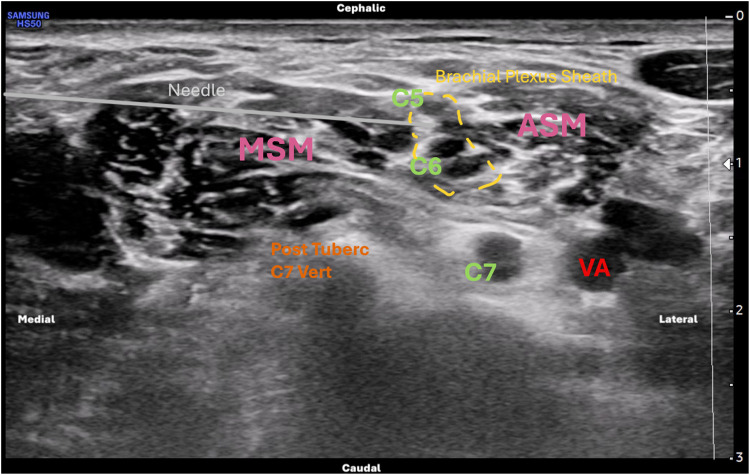

Background and aim: Interscalene Brachial Plexus Block (ISBPB) is commonly used for shoulder surgery anesthesia to reduce opioid use and general anesthesia complications. However, it may cause diaphragmatic paresis due to phrenic nerve involvement. This study compares the incidence of hemidiaphragmatic paralysis and the frequency of side effects-including hemodynamic changes and postoperative complications-between the Extrafascial (ExF) and Intrafascial (InF) approaches for ISBPB using reduced anesthetic volume. The aim is to assess whether the ExF approach may be preferable in patients with reduced cardiopulmonary reserve (eg, COPD or heart failure).

Methods: A retrospective study was conducted at Federico II University in Naples, Italy, including 61 patients undergoing shoulder surgery from January 2024 to October 2024. About 33 patients received ExF while 28 received InF ISBPB, all with Ropivacaine 0.5% (10 mL), Mepivacaine 2% (5 mL), and Dexamethasone (4 mg). The primary outcome was the incidence of hemidiaphragmatic paralysis, evaluated via ultrasound pre and 30 minutes after the block by assessing diaphragm excursion, thickness, and thickening fraction. Secondary outcomes included intraoperative hemodynamic changes and postoperative complications: pain (NRS), analgesic/antiemetic requests, PONV, pruritus, shivering, anxiety, and discomfort.